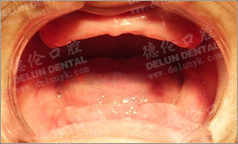

谭智坚医师给祝师奶检查牙齿

谭智坚医生向祝师奶讲解牙片情况